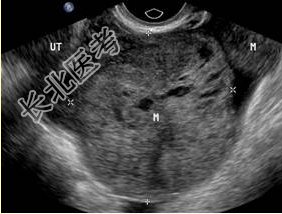

- 单项选择题患者女,55岁, 低热伴下腹胀痛1月余。根据以下声像图表现,以下最可能的诊断是

A、卵巢恶性肿瘤

B、卵巢巧克力囊肿

C、盆腔脓肿

D、卵巢纤维瘤

E、卵巢浆液性囊腺瘤